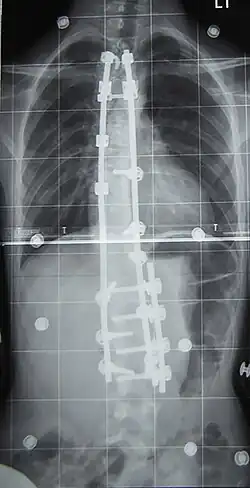

Surgery is usually recommended by orthopedists for curves with a high likelihood of progression (i.e., greater than 45–50° of magnitude), curves that would be cosmetically unacceptable as an adult, curves in people with spina bifida and cerebral palsy that interfere with sitting and care, and curves that affect physiological functions such as breathing.[104][105]

Surgery is indicated by the Society on Scoliosis Orthopaedic and Rehabilitation Treatment (SOSORT) at 45–50°[4] and by the Scoliosis Research Society (SRS) at a Cobb angle of 45°.[106] SOSORT uses the 45–50° threshold as a result of the well-documented, plus or minus 5° measurement error that can occur while measuring Cobb angles.[106]

Surgeons who specialize in spine surgery perform surgery for scoliosis. To completely straighten a scoliotic spine is usually impossible, but for the most part, significant corrections are achieved.[107]

The two main types of surgery are:[108]

- Anterior fusion: This surgical approach is through an incision at the side of the chest wall.

- Posterior fusion: This surgical approach is through an incision on the back and uses metal instrumentation to correct the curve.

One or both of these surgical procedures may be needed. The surgery may be done in one or two stages and, on average, takes four to eight hours.